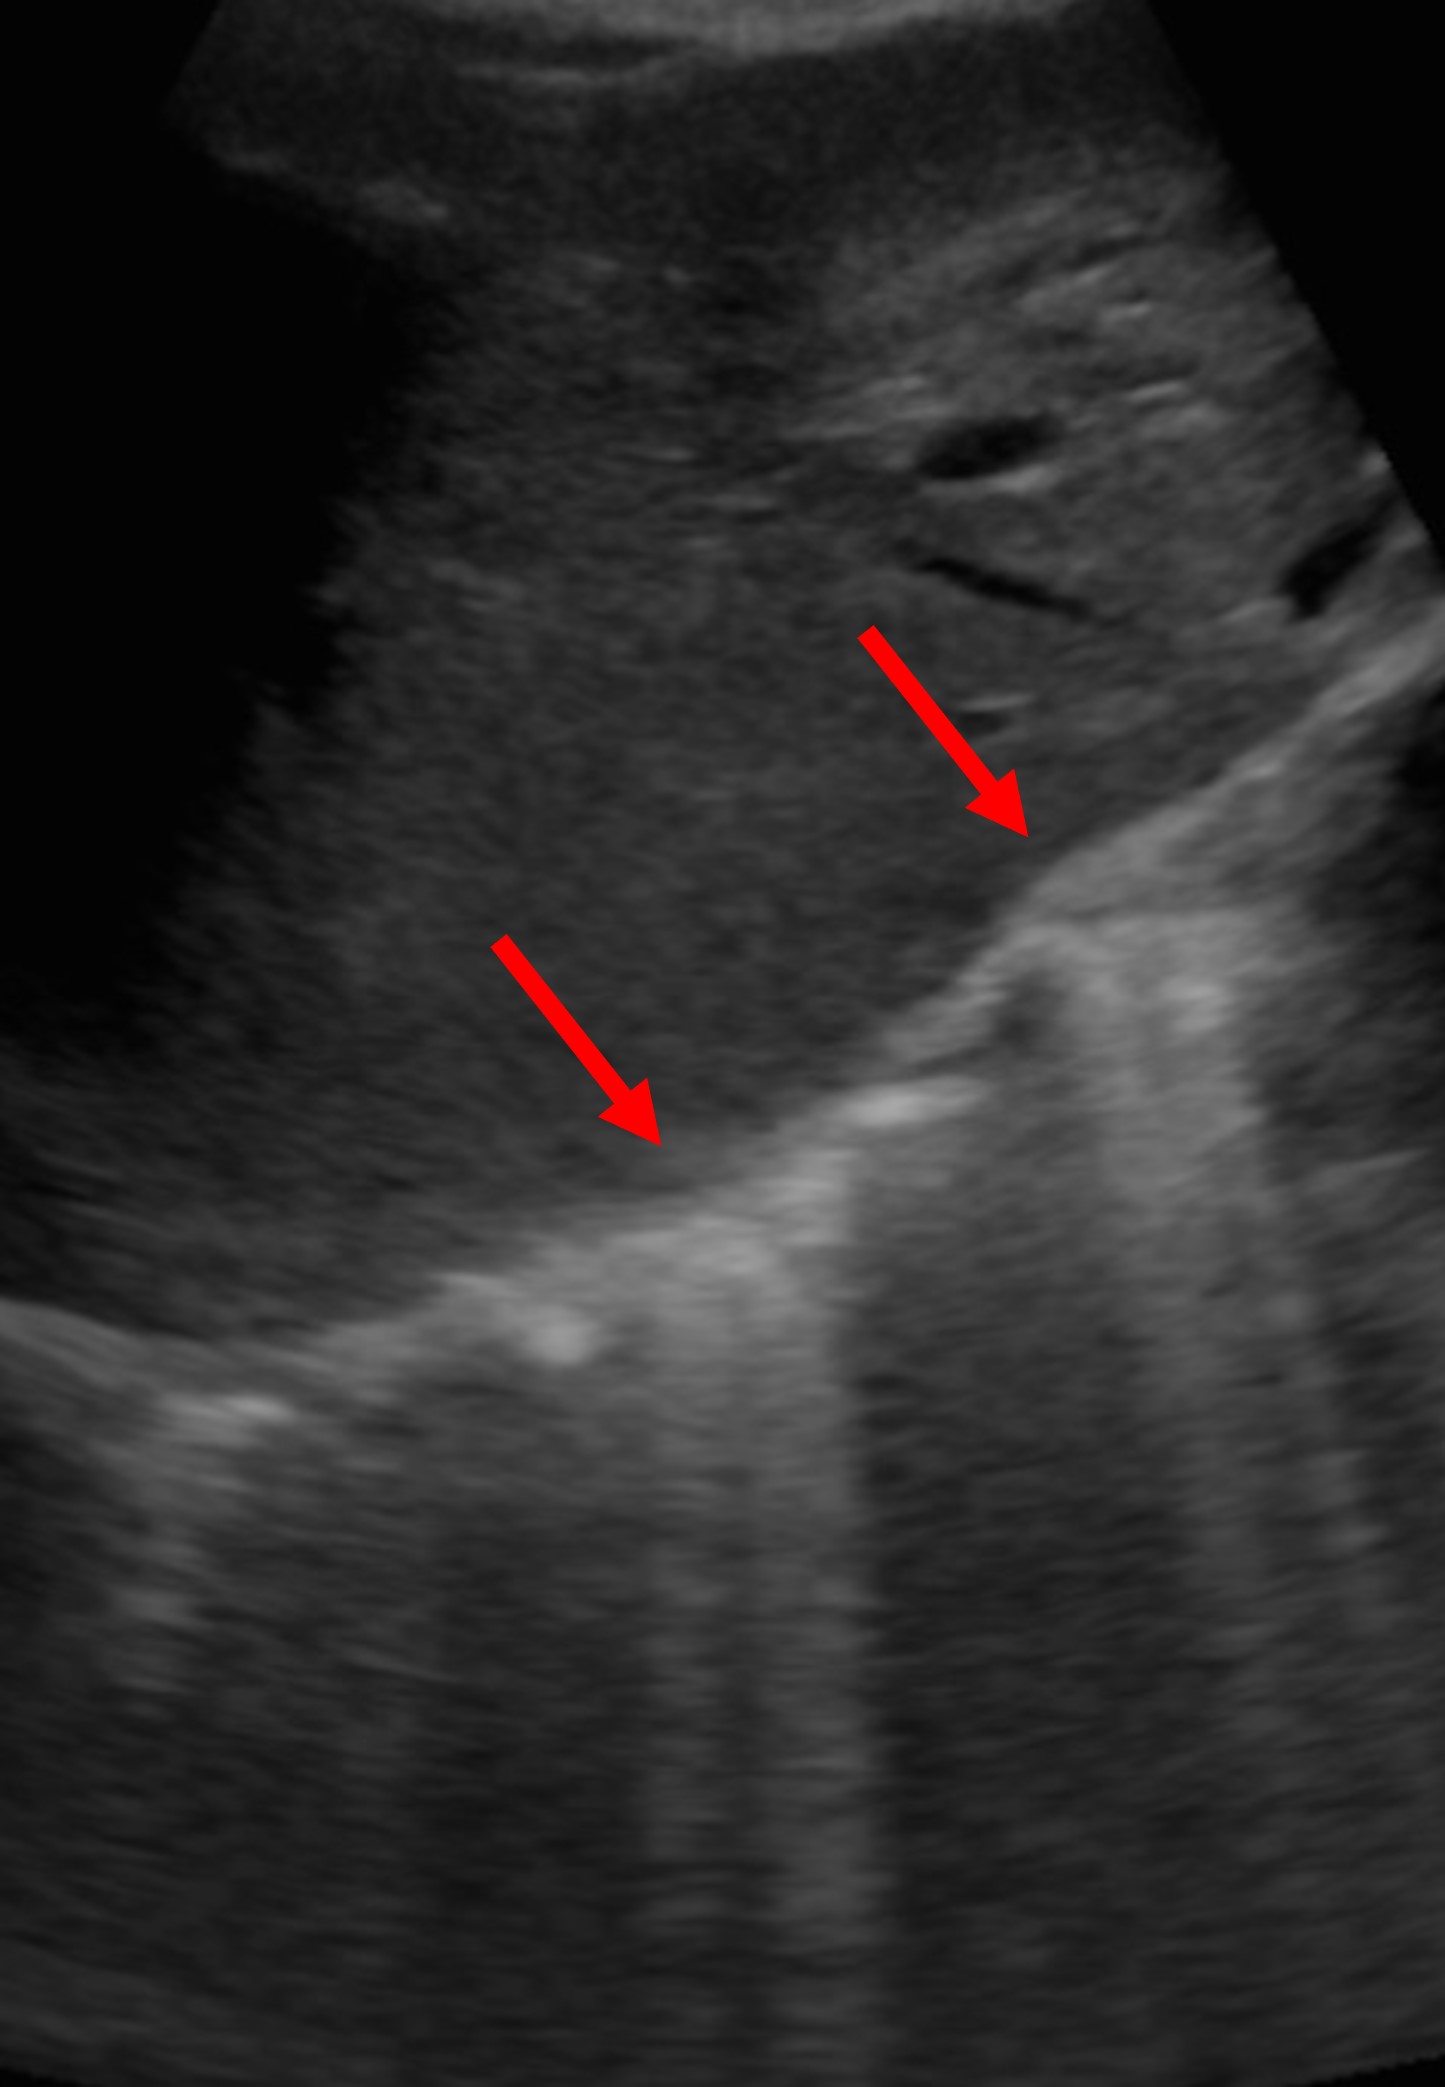

- Er zijn ook 2 specifieke subtypes van het reverberatie artefact: comet-tail artefact en ring-down artefact

- Comet-tail artefact: De sterk reflecterende structuren staan erg dichtbij elkaar, daardoor zijn de opeenvolgende reflecties zo dicht op elkaar dat ze een streep vormen de diepte in. Bijvoorbeeld B-lijnen (weerkaatsing tussen verdikte interlobulaire septa) bij echo van de longen. Ook calcium en corpora aliena kunnen comet-tail artifacten geven

Comet-tail artefact; Afbeeldingen van European Society of Radiology - EPOS